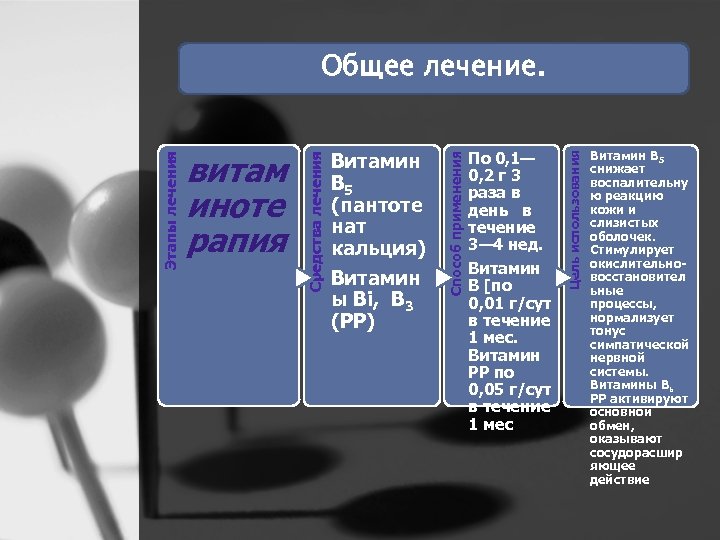

По 0, 1— 0, 2 г 3 раза в день в течение 3— 4 нед. Витамин В [по 0, 01 г/сут в течение 1 мес. Витамин РР по 0, 05 г/сут в течение 1 мес Цель использования Витамин В 5 (пантоте нат кальция) Витамин ы Bi, B 3 (РР) Способ применения витам иноте рапия Средства лечения Этапы лечения Общее лечение. Витамин В 5 снижает воспалительну ю реакцию кожи и слизистых оболочек. Стимулирует окислительно восстановител ьные процессы, нормализует тонус симпатической нервной системы. Витамины Вь РР активируют основной обмен, оказывают сосудорасшир яющее действие